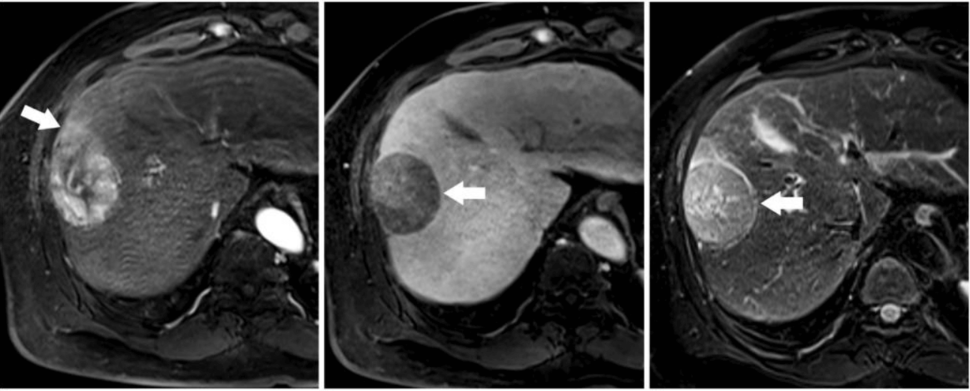

A series of three liver MRI images labeled A, B, and C showing different imaging sequences of the same liver with a mass (indicated by white arrows in each image). Each image shows the same liver lesion with different contrast and visibility depending on the MRI sequence used

MRI images of a primary liver tumor.

Credit: Cho ES. Korean J Radiol May 2015, doi: 10.3348/kjr.2015.16.3.449